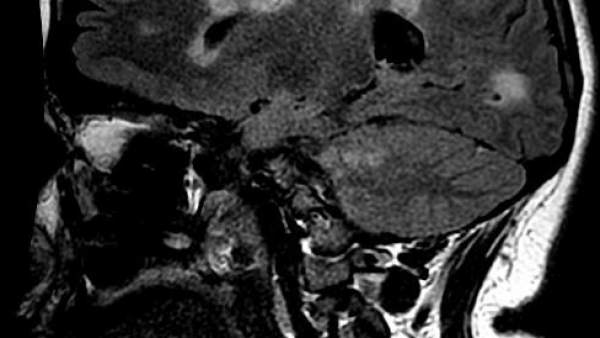

La esclerosis múltiple puede estar latente en tu cuerpo, generándose en tu cerebro o médula espinal, y no percatarte de sus daños hasta que se manifiesta en forma de brote, tal y como han experimentado numerosos afectados. Una pierna dormida de manera prolongada, visión doble, cefaleas continuas, incluso dificultades en el habla, hasta la inmovilidad total de algunas articulaciones del cuerpo y el mal funcionamiento de algún órgano son algunos de sus efectos.

Esta enfermedad autoinmune y neurodegenerativa desmielinizante provoca daños en la capa de mielina de las fibras nerviosas provocando un mal funcionamiento de órganos y músculos.

Durante muchos años ha sido considerada una enfermedad de sustancia blanca del sistema nervioso central aunque un número creciente de estudios haya demostrado que también afecta a la materia gris.

En la esclerosis múltiple se verifica un daño y una pérdida de mielina en varias áreas -de ahí el nombre de múltiple- del sistema nervioso central. Numerosas evidencias sean clínicas o experimentales indican que existe un proceso de desmielinización que determina daños o pérdida de la mielina y la formación de lesiones (placas).

Estas pueden cambiar de una fase inflamatoria inicial a una crónica, en la cual provoca características similares a las cicatrices, de ahí la denominación ‘esclerosis’, que significa «endurecimiento patológico de un órgano o tejido».